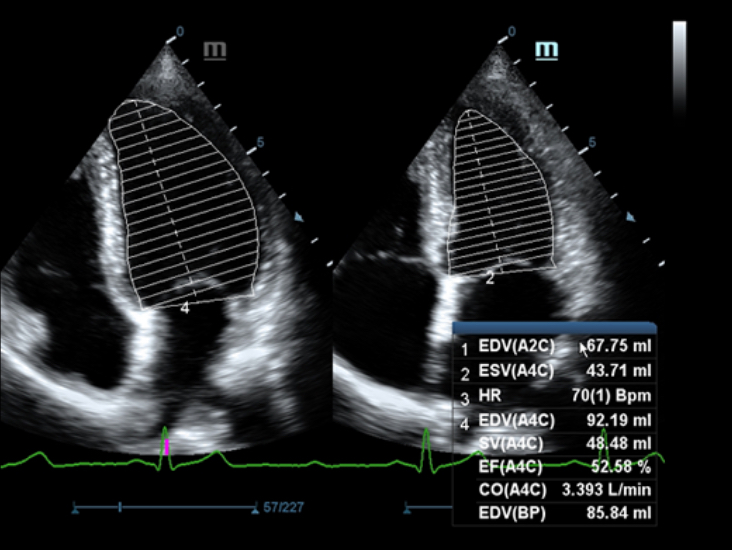

-Auto EF

Auto EF is an intelligent way to analyze 2D echo clips to automatically recognize diastole & systole frames and output a series of measurements to evaluate left ventricle function for more productivity, such as EDV/ESV/EF.